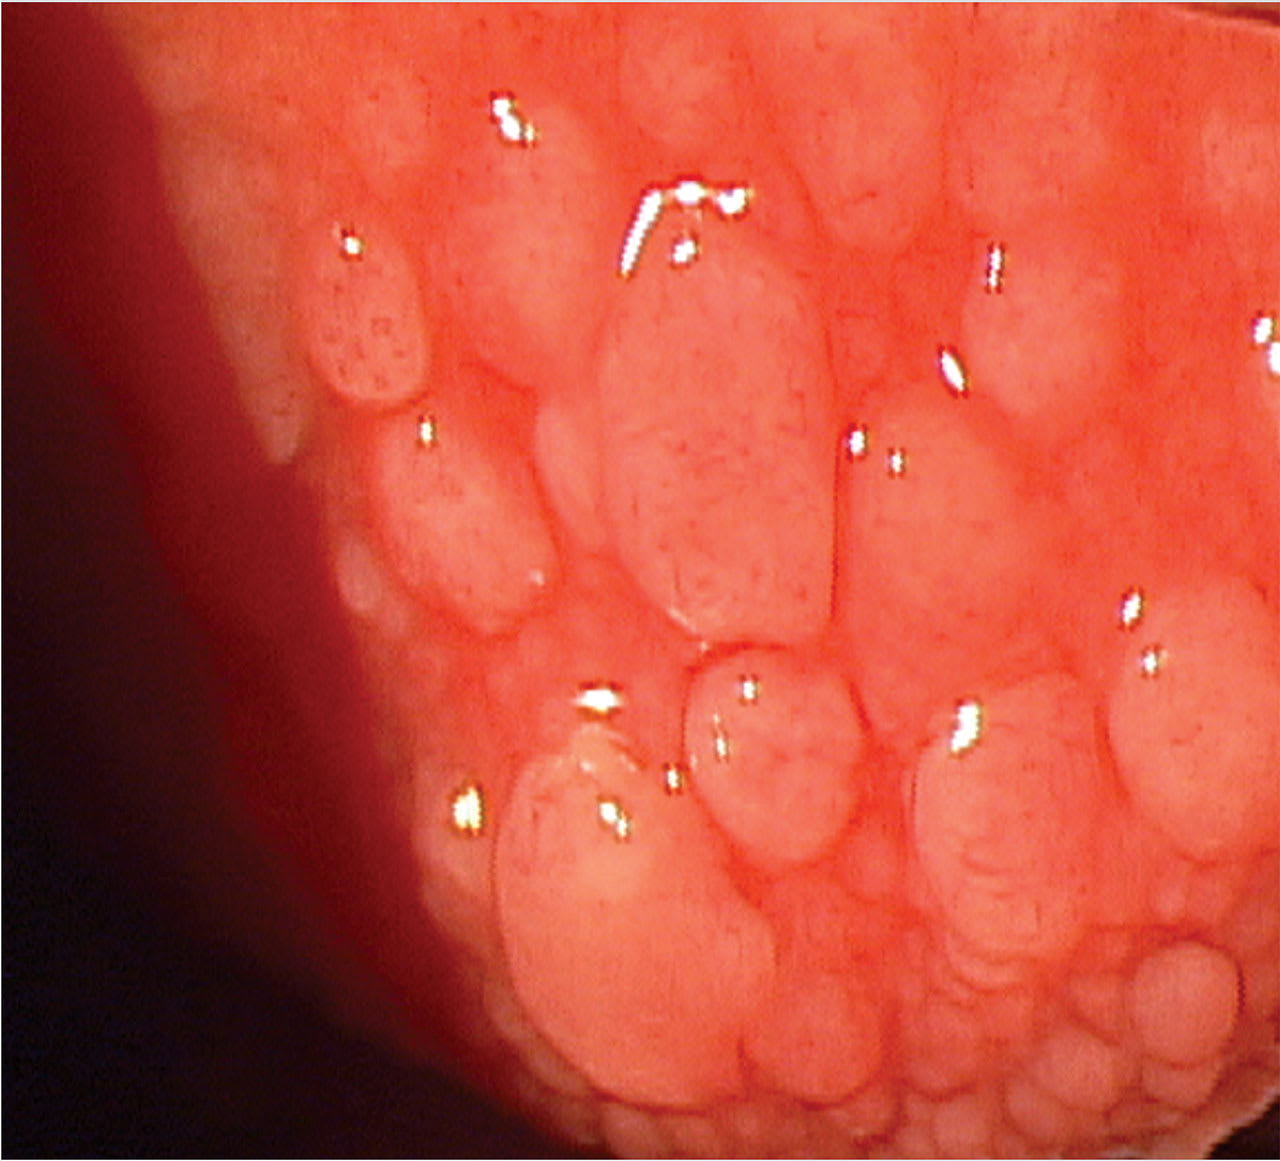

2. Look at the lids/ocular surface. A slit lamp examination of the lids can also aid in arriving at an accurate diagnosis. In ocular allergy, the lid will generally be swollen with papillae and have a velvety appearance. Additionally, the cornea may be involved superiorly. In advanced vernal keratoconjunctivitis, the superior cornea may be significantly affected due to inflammatory cell infiltration, mechanical damage from large papillae on the upper eyelid, and the release of toxic inflammatory mediators, leading to neovascularization, formation of shield ulcers, and scarring.1